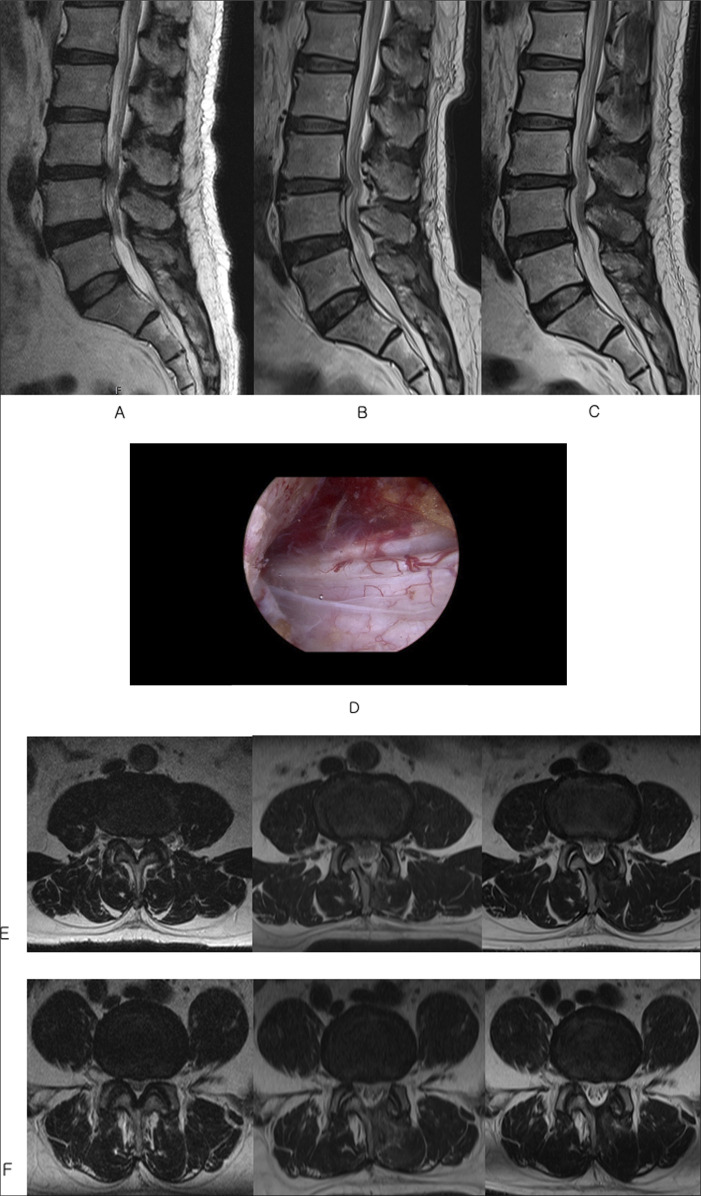

研究设计:回顾性。目的:比较单侧双门静脉内窥镜(UBE)单节段减压与多节段减压治疗退行性腰椎管狭窄无不稳定性的长期临床效果。背景资料总结:单侧双门静脉内窥镜减压已被证明可以有效缓解椎管狭窄而不不稳定。缺乏长期的数据,特别是,使用这种微创技术的单节段和多节段手术之间的比较尚未提出。方法:每组98例患者进行人口统计学倾向匹配。所有患者至少进行了5年的随访。临床结果包括Oswestry残疾指数、视觉模拟系统(VAS)、行走时间、手术时间和住院时间。结果:单节段减压组的Oswestry功能障碍指数由术前的62.98±11.53改善至最后随访时的18.51±8.63 (P < 0.001)。多节段减压从64.66±13.71改善到19.31±9.42 (P < 0.001)。同样,单节段减压后,下肢和背部VAS从术前的7.39±0.91和6.11±1.21降至末次随访时的1.72±0.548和1.82±0.67 (P < 0.001)。相比之下,对于多水平,腿部和背部VAS从7.47±1.09和6.29±1.28改善到1.86±0.58和1.91±0.75 (P < 0.001)。各组之间在任何时间点均未观察到差异。并发症和翻修率无差异。多节段患者行走时间和停留时间明显延长。结论:结果、并发症和翻修率在单节段和多节段之间没有差异。如果认为有必要进行多级减压,则UBE减压可以应用于多个级别,而不会影响结果。

Study design: Retrospective.

Objective: To compare long term clinical outcomes of single-level versus multilevel decompression using unilateral biportal endoscopic (UBE) decompression for degenerative lumbar spinal stenosis without instability.

Summary of background data: Unilateral biportal endoscopic decompression has been shown to be effective in alleviating spinal stenosis without instability. Long-term data are lacking, and, in particular, a comparison between single-level and multilevel surgery using this minimally invasive technique has not been presented.

Methods: Ninety-eight patients in each group were propensity matched based on demographics. All patients had at least 5-year follow-up. Clinical outcomes, including Oswestry Disability Index, visual analog system (VAS), time to ambulation, surgical time, and length of hospital stay, were investigated.

Result: Oswestry Disability Index improved from 62.98 ± 11.53 before surgery to 18.51 ± 8.63 at the final follow-up in single-level decompression (P < 0.001). Multilevel decompression demonstrated improvement from 64.66 ± 13.71 to 19.31 ± 9.42 (P < 0.001). Similarly, leg and back VAS decreased from 7.39 ± 0.91 and 6.11 ± 1.21 before surgery to 1.72 ± 0.548 and 1.82 ± 0.67 at the last follow-up (P < 0.001) for single-level decompression. In comparison, for the multilevel, leg and back VAS improved from 7.47 ± 1.09 and 6.29 ± 1.28 to 1.86 ± 0.58 and 1.91 ± 0.75 (P < 0.001). No difference was observed between the groups at any time point. Complications and revision rates did not differ. Time to ambulation and length stay was markedly longer in multilevel.

Conclusion: Outcomes, complication, and revision rates do not differ between single level and multilevel. UBE decompression can be applied to multiple levels without compromising outcomes if multiple-level decompression is deemed necessary.